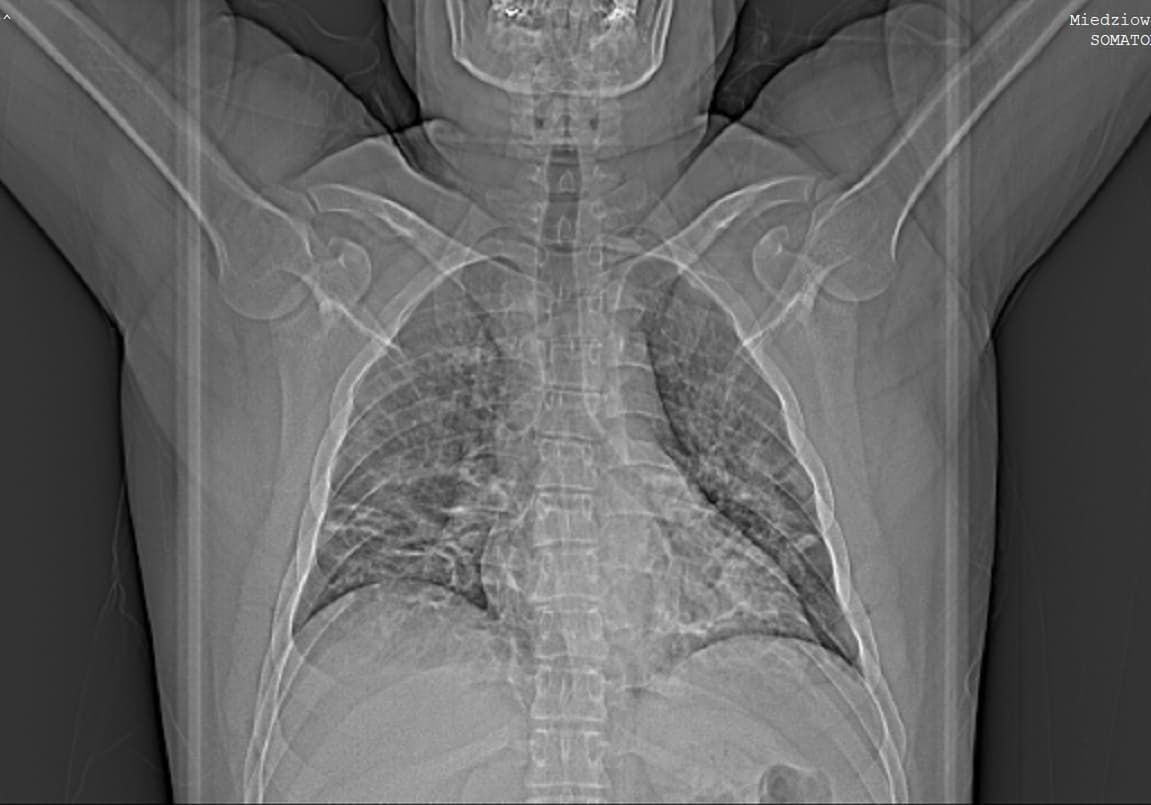

COVID-19. Lekarze stwierdzili, że jego płuca wyglądają, jakby ktoś wstawił w nie mleczną szybęCOVID-19. Lekarze stwierdzili, że jego płuca wyglądają, jakby ktoś wstawił w nie mleczną szybę

COVID-19. Jego płuca wyglądały, jakby ktoś wstawił w nie mleczną szybę

- Mówili mi, że jestem w czepku urodzony, bo od razu znalazło się dla mnie miejsce. Nie było już ze mną za ciekawie. W szpitalu na tomografii wyszło, że mam obustronne zapalenie płuc, płuca wyglądają, jakby ktoś wstawił w nie mleczną szybę. Pamiętam, że bardzo mi pomógł tlen, bo bez niego nie mogłem wziąć oddechu. Poprawiła się saturacja. Dostałem antybiotyki oraz sterydy. W pierwszych dniach w szpitalu nie mogłem się ruszyć z łóżka z powodu duszności, bólu, zawrotów głowy, osłabienia, nie mogłem patrzeć na jedzenie z powodu drażniących zapachów, które powodowały kaszel i duszność. Badania wykazały, że mam hipoksemię, wysokie CRP i leukocytozę.